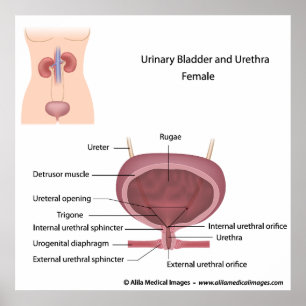

Hondjurens urinvägssystem, märkt poster

Pris705,00 kr